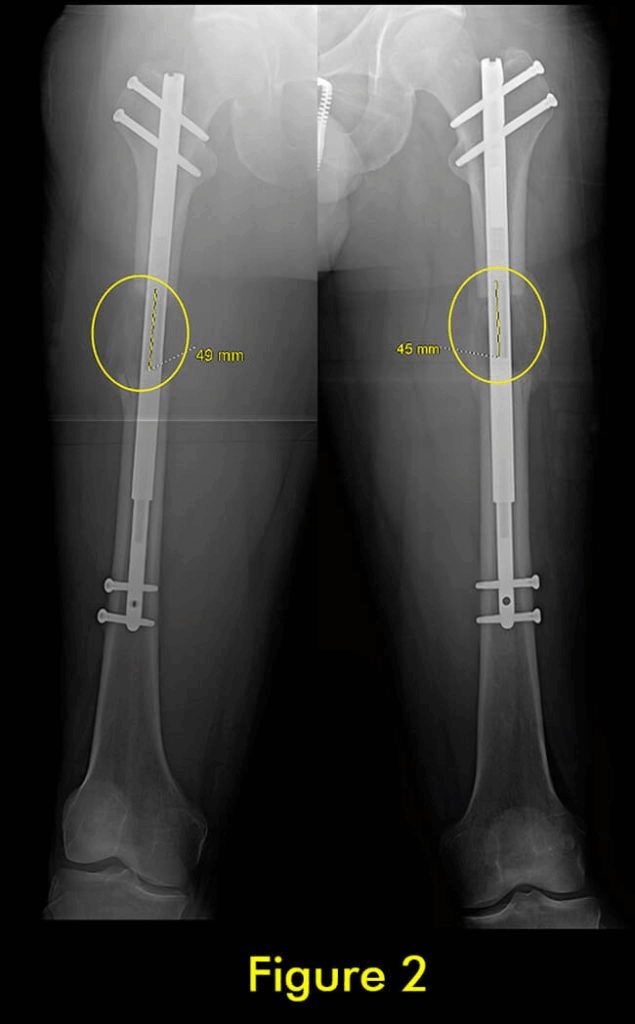

图1:延长量细微差异

图2:X光片确认诊断